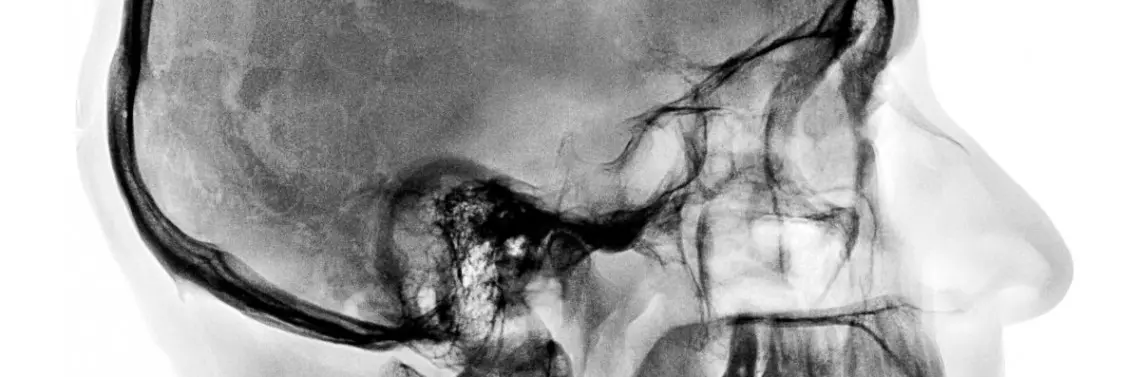

• Leczenie dostosowane jest do rozpoznania i dotyczy: kości skroniowej, mięśni żucia (np. poprzez delikatne rozciąganie lub izometryczne napinanie mięśni), mięśni gnykowych i mięśni karku, stawu szczytowo-potylicznego, powięzi czaszkowo-szyjnych, kłykci i krążków stawowych, więzadła klinowo-żuchwowego, rylcowo-żuchwowego, klinowo-skalistego, desensytyzacji (desensybilizacji) nerwu żuchwowego, zwoju trójdzielnego i odpowiedniego regionu jąder rdzeniowych, a także nerwu twarzowego.